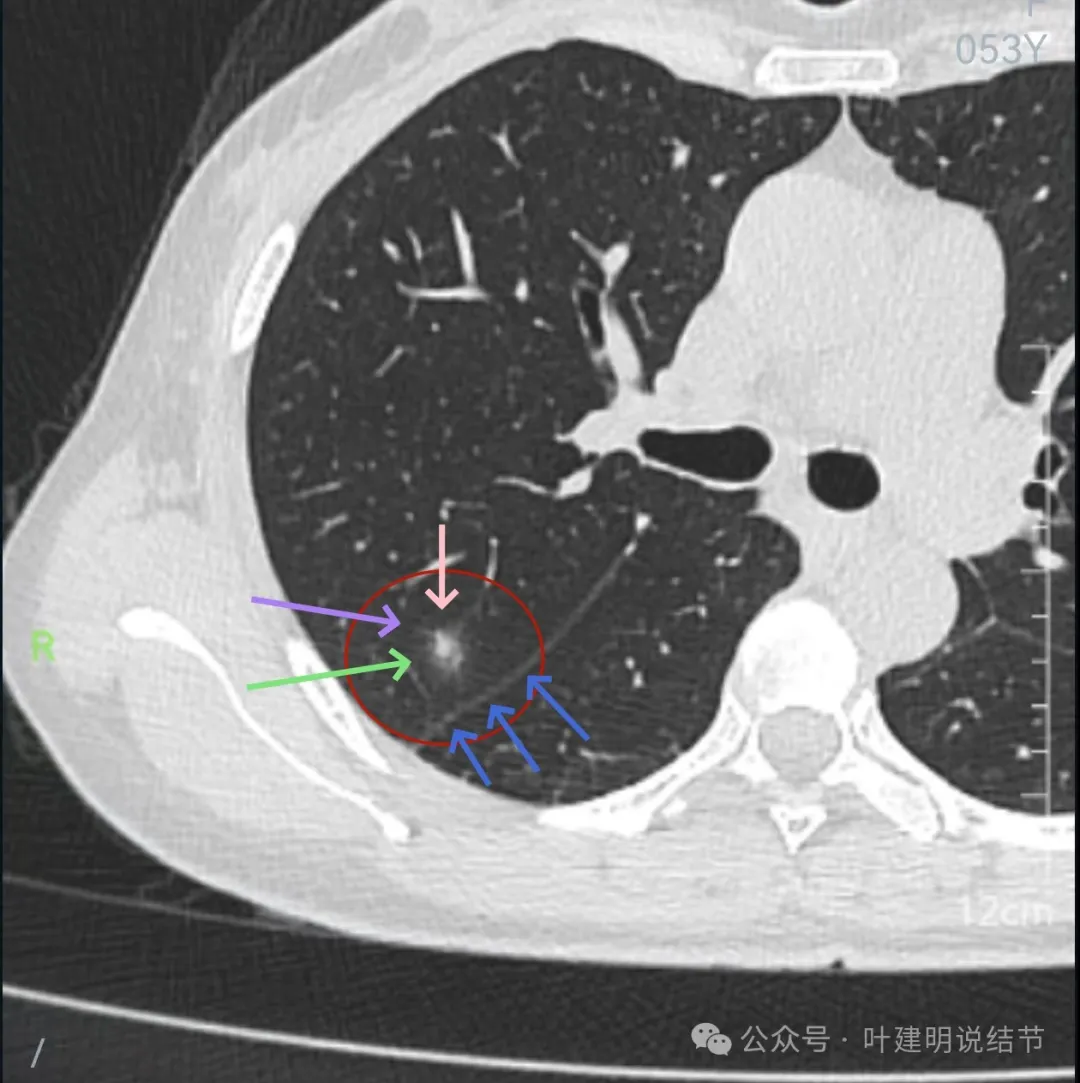

再来看周教授认为4B类的右上后段病灶连续层面影像信息:

病灶出现,轮廓不清,瘤肺边界模糊,有血管穿行,血管有异常增粗。

血管壁有异常密度增高,病灶混合密度,轮廓总体在此层较清,但瘤肺边界不清。

病灶偏实性部分不密实,磨玻璃部分过淡且模糊。

边缘有毛刺,但不够锐利;外周磨玻璃成分密度过淡且界限不清;实性部分也显得不致密;与叶间裂距离近但没有任何牵拉影响。

实性成分在灶内看,也是界限不清,磨玻璃部分淡而糊。

整体感觉像病灶中间偏实性些的成分伴外周晕征。

边缘区域离叶间裂更近,仍无牵拉。

几乎贴着叶间裂了,仍无任何牵拉影响。

病灶密度边缘部分也不均,离叶间裂近而没有影响。

上图病灶已经贴着叶间裂,但仍显示是平直的,没有任何牵拉影响。

矢状位上看,病灶虽整体轮廓较清,但瘤肺边界显模糊,整体不致密。

冠状位上看病灶有实性成分,实性成分缺乏收缩力,外围是淡磨玻璃成分,瘤肺边界欠清,贴着叶裂没有影响。

从连续层面以及影像细节上看,这个病灶就不可能是恶性的!短期内出现,混合密度而瘤肺边界不清,整体缺乏收缩力也无膨胀性,灶内实性成分不致密且磨玻璃成分过淡,灶内血管有异常增粗与密度过高,又是两肺多发病灶。这所有的表现与病情发展都与感染性病变契合,周围淡磨就是炎症水肿的关系,血管异常就是管壁有炎症的关系,多发就是感染(致病因素)影响两肺的关系。怎么可能是恶性?